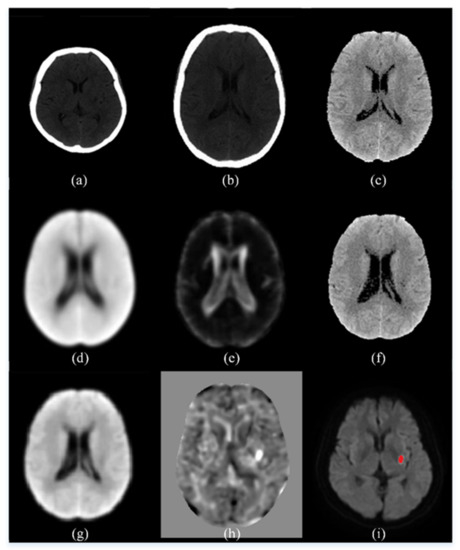

Shown in Figure 3 are some intermediate images produced during the preprocessing steps. The images in the top row are, from left to right, an original control CT image, the result of the spatial normalization (Step C3), and the result of intensity transformation (Step C4). The images in the central row are, from left to right, the average CT map of all control CT (Step C10), the standard deviation CT map of all control CT (Step C10), and a patient CT image after normalization to our own CT template (Step P3). The images in the bottom row are, from left to right, the result of spatial smoothing by the kernel with a 5-mm FWHM (Step P6), the t-score map (Step P7), and the ischemic infarct area drawn by the clinician.

Figure 3. An illustration of the intermediate images in the image preprocessing steps. (a) An original control CT image; (b) the result of the spatial normalization; (c) the result of intensity transformation; (d) the average CT map of all control CT; (e) the standard deviation CT map of all control CT; (f) a patient CT image after normalization to our own CT template; (g) the result of spatial smoothing by the kernel with a 5-mm FWHM; (h) the t-score map; (i) the ischemic infarct area drawn by the experienced neurologist.